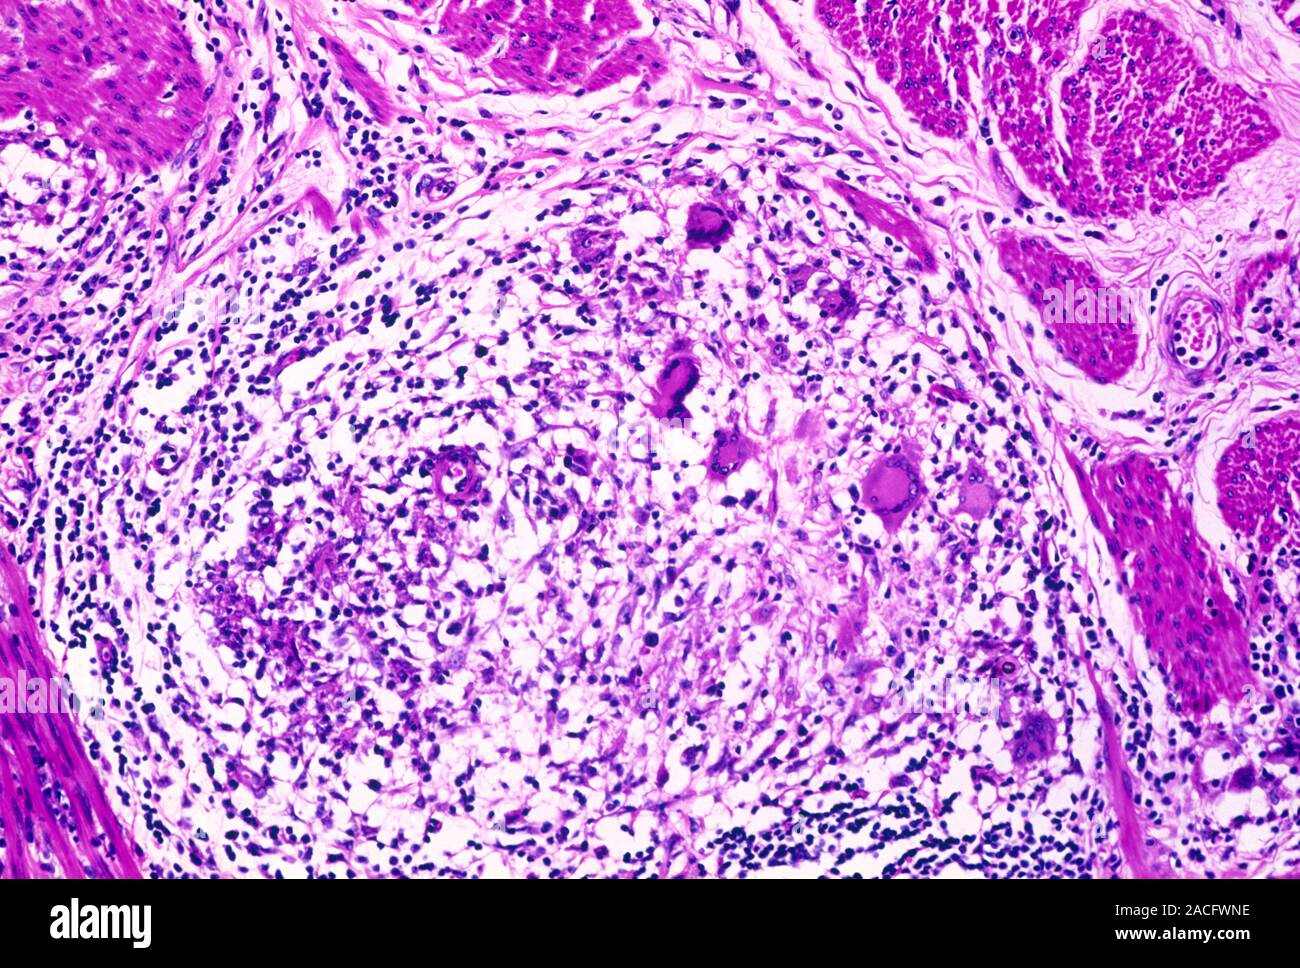

Chronic colitis with a granuloma surrounded by numerous immune cells Crohn's Disease Granuloma a granuloma is a collection of wbcs that help your body fight off infection. the presence of granulomas in the gastrointestinal (gi) tract is one of the characteristic histologic features of. However, the clinical significance of. Granulomas create a protective barrier around bacteria or foreign. granulomas are a common symptom of crohn’s disease and may help doctors. Crohn's Disease Granuloma.